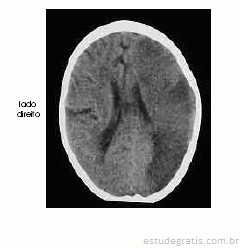

Um homem com 67 anos de idade, lavrador, deu entrada no pronto-socorro após ter sido encontrado, em sua casa, no chão e com dificuldade para falar e deambular. O paciente morava sozinho e os parentes não sabiam informar sobre uso de medicações ou patologias pregressas. Na avaliação, o neurologista identificou afasia mista, hemianopsia homônima direita e hemiparesia direita de predomínio braquifacial. Apesar de apresentar sonolência, o paciente ficava alerta ao chamado. A pressão arterial era de 180 mmHg × 90 mmHg. Foram solicitados exames complementares e de imagem, dos quais uma das imagens é reproduzida abaixo.

A hemorragia subaracnóide é causa de cefaléia e convulsões. Uma complicação desse tipo de sangramento é o vasoespasmo, que pode causar acidente vascular cerebral isquêmico e resultar em quadro clínico semelhante ao ilustrado.